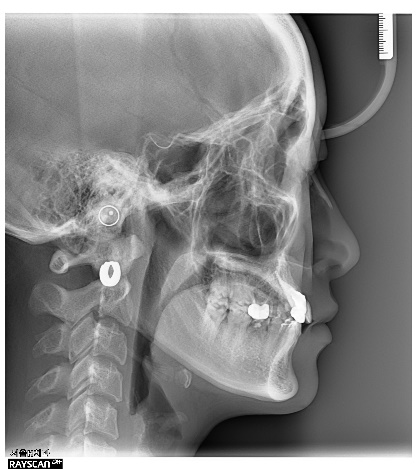

이 환자는 19세 여환으로 multiple congenitalmissing을 가지고 있으나 전치부 반대교합과 spacing의 해결만을 위해 내원하였습니다. 부분교정 시행후 상악 양측측절치 부위를 임플란트로 식립하기로결정하였습니다.

상악 양측 견치의 수직적 위치가 다른 것을 알 수 있습니다. 이는 추후 교정치료가마무리되면 전치부 교합평면의 canting이 확연히 보이게 되므로 문제가 될 수 있습니다.